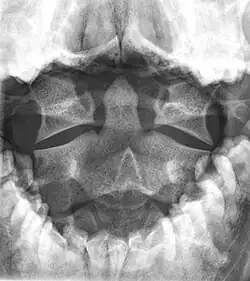

Der Axis unterscheidet sich durch seine Form von allen anderen Wirbeln. Der Wirbelkörper ist relativ groß und massiv. Hervorstechendes Merkmal ist der Dorn oder Zahn des Axis (Dens axis) auf der Oberseite vorne (Mensch) beziehungsweise Vorderseite (vierfüßige Säugetiere) des Wirbelkörpers. Er stellt ontogenetisch den Wirbelkörper des Atlas dar und liegt genau dort, wo diesem fast ringförmigen Wirbel der Körper fehlt. Der Dens geht von der Oberseite des Wirbelkörpers gerade nach oben, besitzt auf seiner Vorder- und Rückseite eine Gelenkfläche und endet mit einer abgerundeten Spitze.[1]

Auf beiden Seiten des Axis geht je ein kurzer Querfortsatz (Processus transversus) ab, der halswirbeltypisch eine runde Öffnung (Foramen transversarium) für die Wirbelarterie umschließt. Rückenseitig schließt sich der ebenfalls recht massive Wirbelbogen an, dessen Ende den kurzen, gegabelten Dornfortsatz (Processus spinosus) trägt. Auf der Ober- und Unterseite liegen je zwei Gelenkfortsätze (Processus articularis superior beziehungsweise inferior) für die Verbindung mit den beiden angrenzenden Wirbeln.[1]

Frakturen des zweiten Halswirbels machen etwa ein Fünftel bis ein Viertel aller Halswirbelverletzungen aus, etwa 60 % davon sind Frakturen des Dens axis. Besteht bei einem Unfallopfer der Verdacht auf einen Genickbruch, muss eine Intubation vorsichtig vorgenommen werden, möglichst in Neutralstellung. Der verschobene Wirbel wird meist von vorn mit Hilfe zweier Zugschrauben (ventrale Kompressionsosteosynthese) fixiert.[2] Atlanto-occipitale Dislokationen können mit Hilfe des Dens-Basion-Intervalls quantifiziert werden. Im normalen Röntgenbild sollte der Abstand zwischen der Spitze des Dens axis und dem Basion weniger als 12 mm betragen.[3]